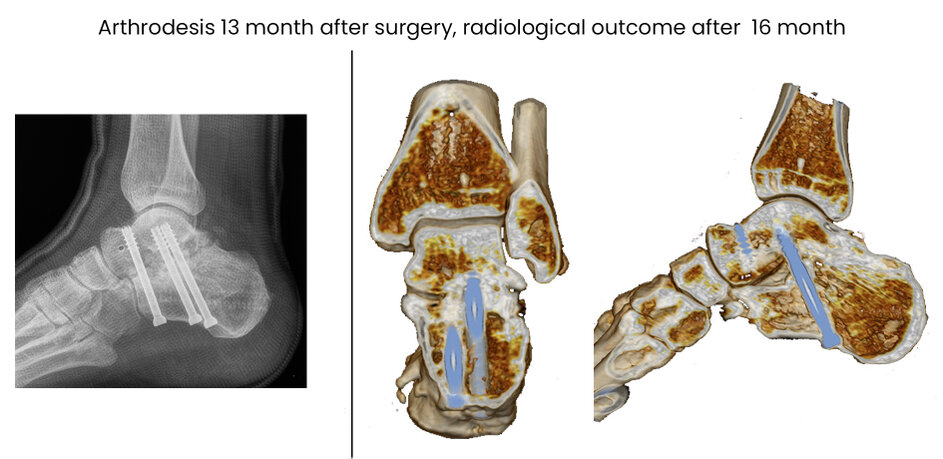

14CE, male 52 y, comminuted, MIT,surgery 2 days after trauma, secundary arthrodesis